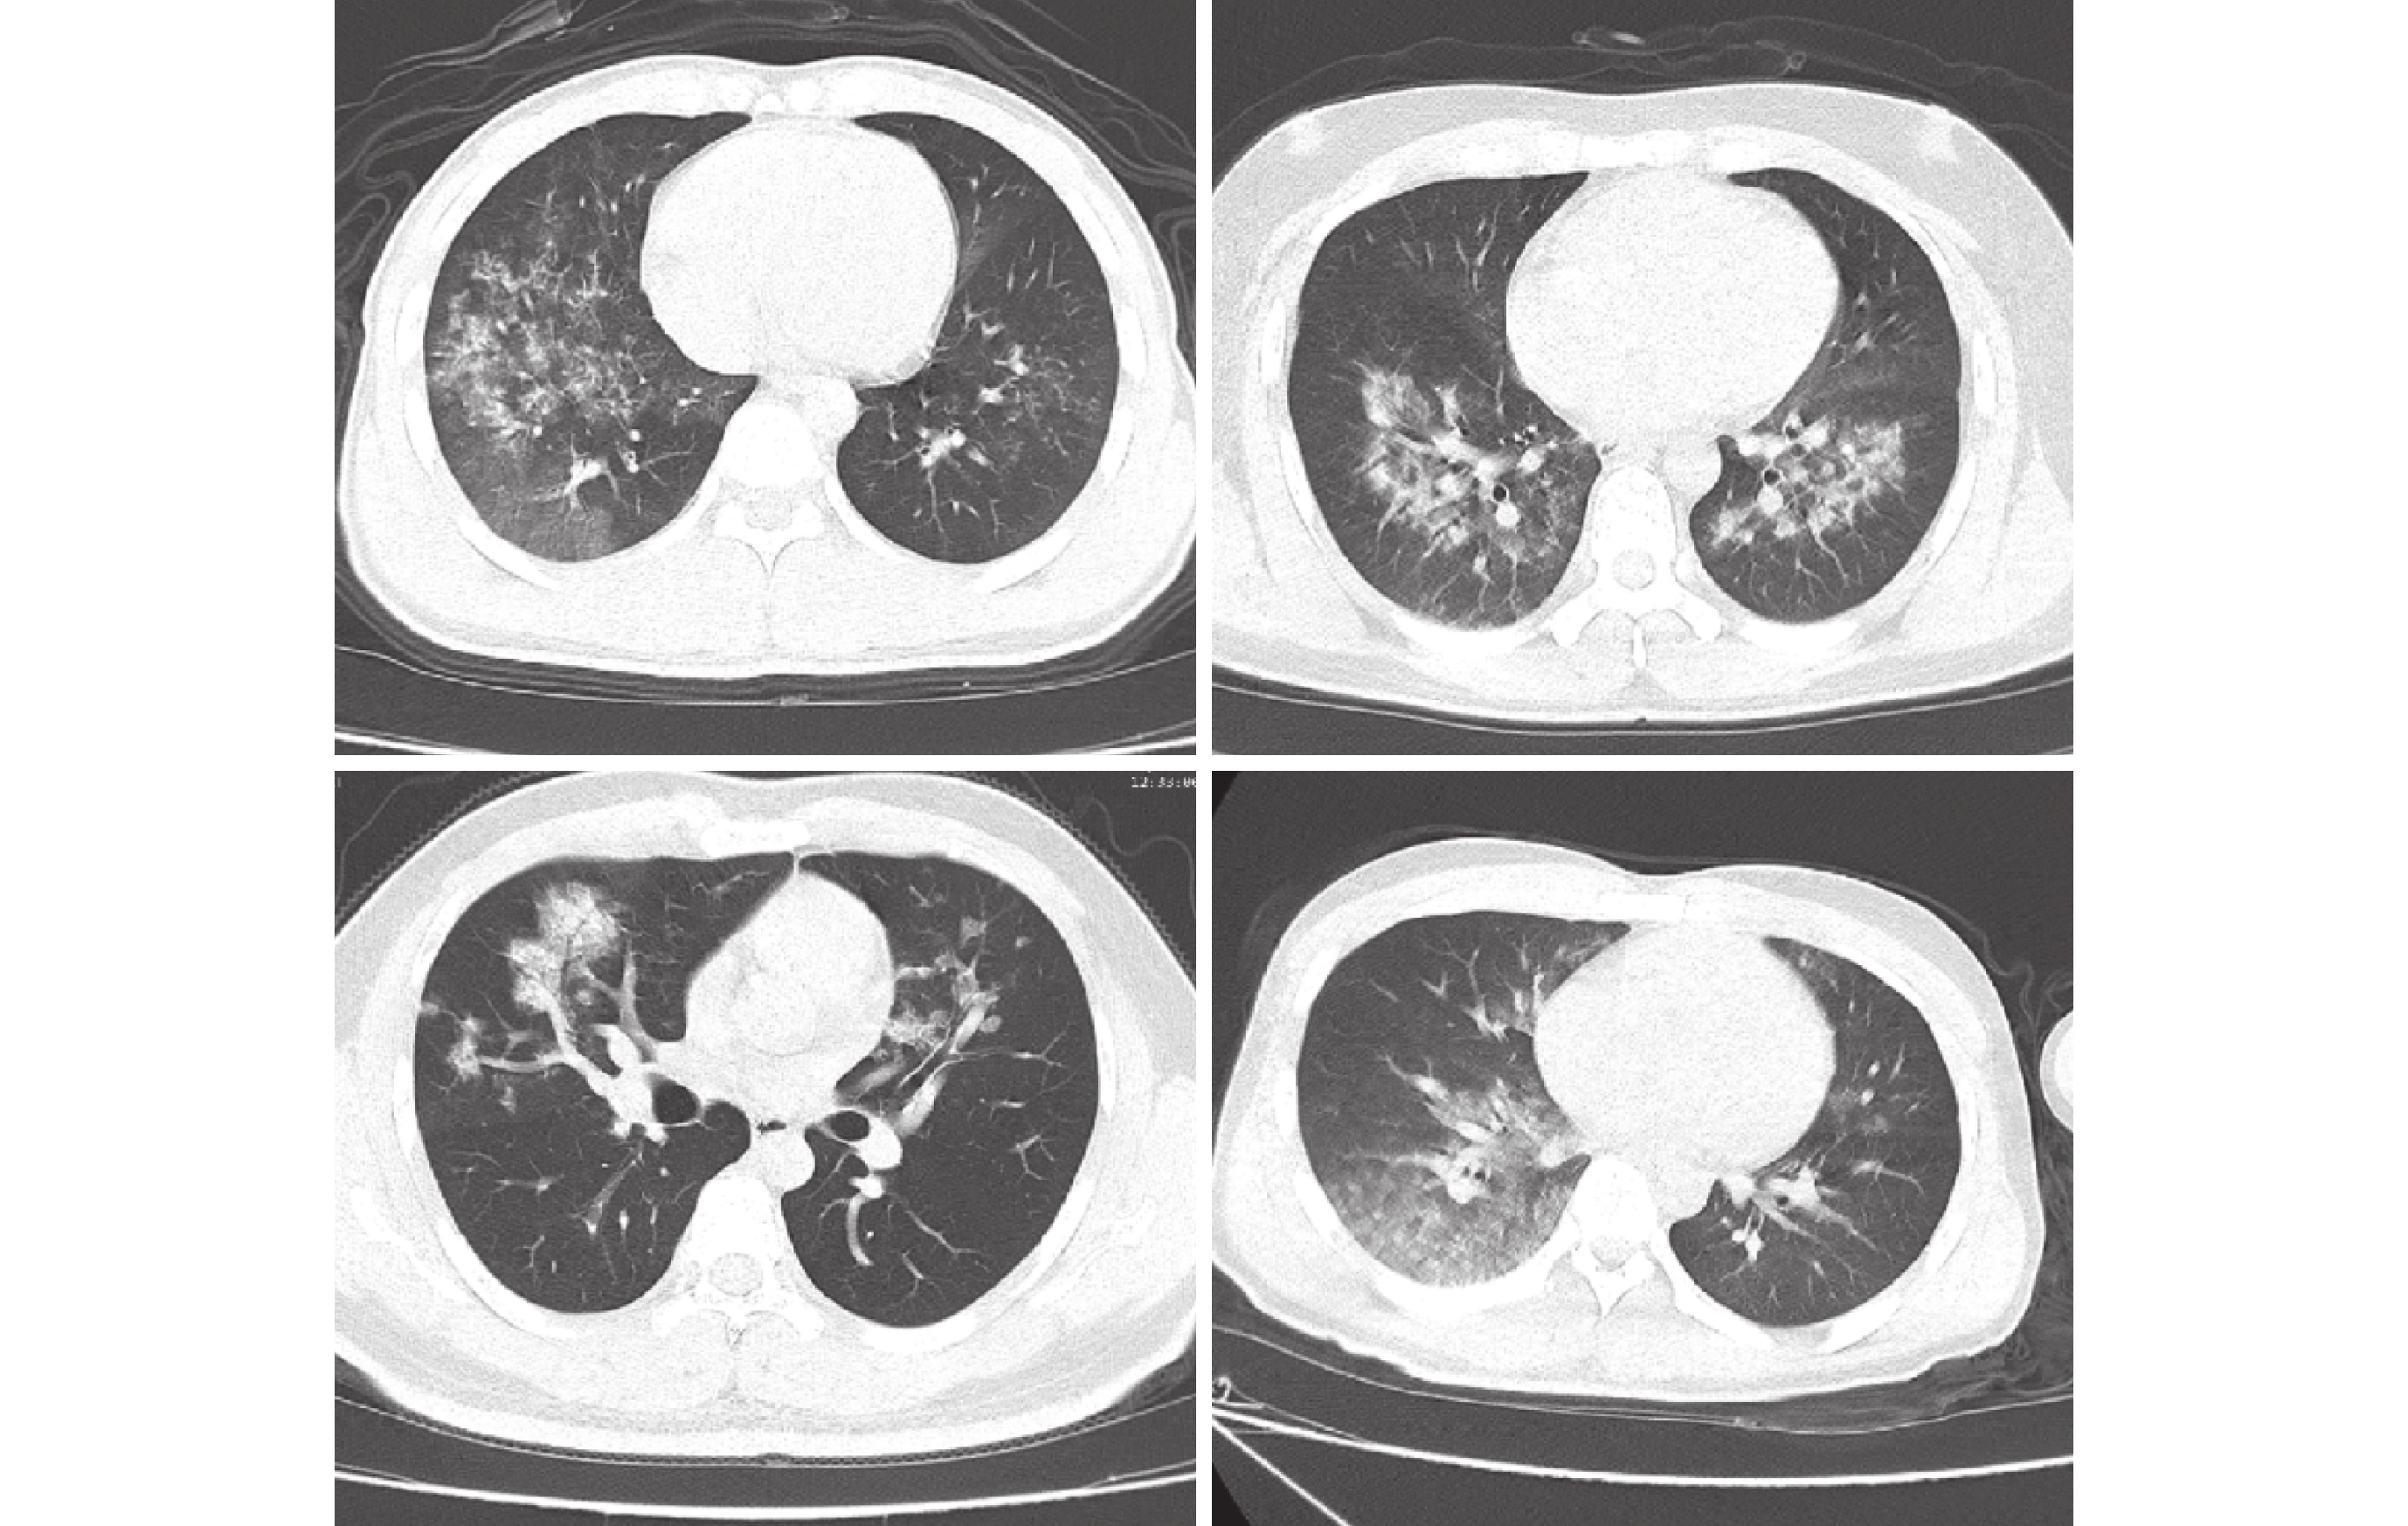

2.2.1 早期

CT 表現為磨玻璃影伴隨密度增高,多出現于雙肺下葉背段及右中葉外側和后基底段,且左下葉多晚于右下葉(見圖 1)。

2.2.2 進展期

如果早期治療不當或不及時,病變密度繼續增加,范圍繼續擴大,CT 表現為云絮狀密度增高影,常以右肺下葉背段或右中葉為重(見圖 2)。